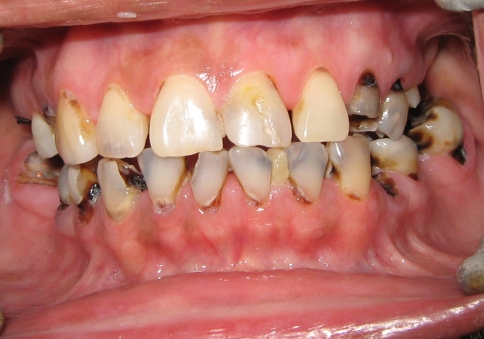

Oral examination showed multiple grossly decayed teeth and reduced vertical dimension of occlusion with 7 mm free way space (Fig. 1). Teeth # 17, 26, 27, 36, 46 were missing and teeth # 16, 45, 47 were extracted because of periapical pathologies and extensive coronal structure loss [9]. Routine endodontic treatment of teeth with carious exposures (# 14, 23, 25, 31, 32, 34, 35, 37, 41, 42, 43, 44) was done followed by post and core build up (C-Post, Bisco Inc, Schamburg, Illinosis) in teeth # 14, 31, 32, 34, 35, 37, 41, 42, 43, 44 as most of their coronal tooth structure was destroyed [10]. Teeth # 23, 25, 33 required core restorations with composite resin (Filtek Z250, 3M ESPE, St. Paul, Minnesota). Teeth with minor carious involvement (# 13, 12, 11, 21, 22) were restored with light cured Glass ionomer cement (Fuji LC GC, Alsip, Illinosis).

Fig. 1.

Pre-operative intraoral view